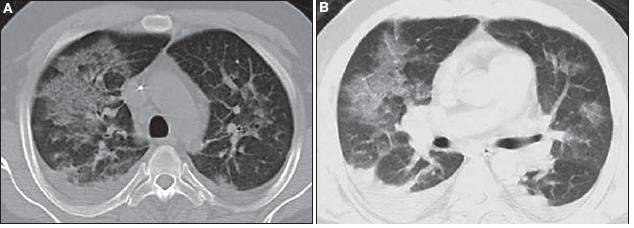

Chest CT scanning revealed patchy ground-glass opacities bilaterally, but greater on the right than on the left; evidence of early consolidation in the right lower lung; mediastinal lymphadenopathy with bilateral hilar fullness; and bilateral small pleural effusions (Figure 2).

Figure 2 – Patchy ground-glass opacities are evident on these CT scans of the chest (Figure B is the lower cut). There also is evidence of early consolidation in the right lower lung, mediastinal lymphadenopathy with bilateral hilar fullness, and bilateral small pleural effusions.